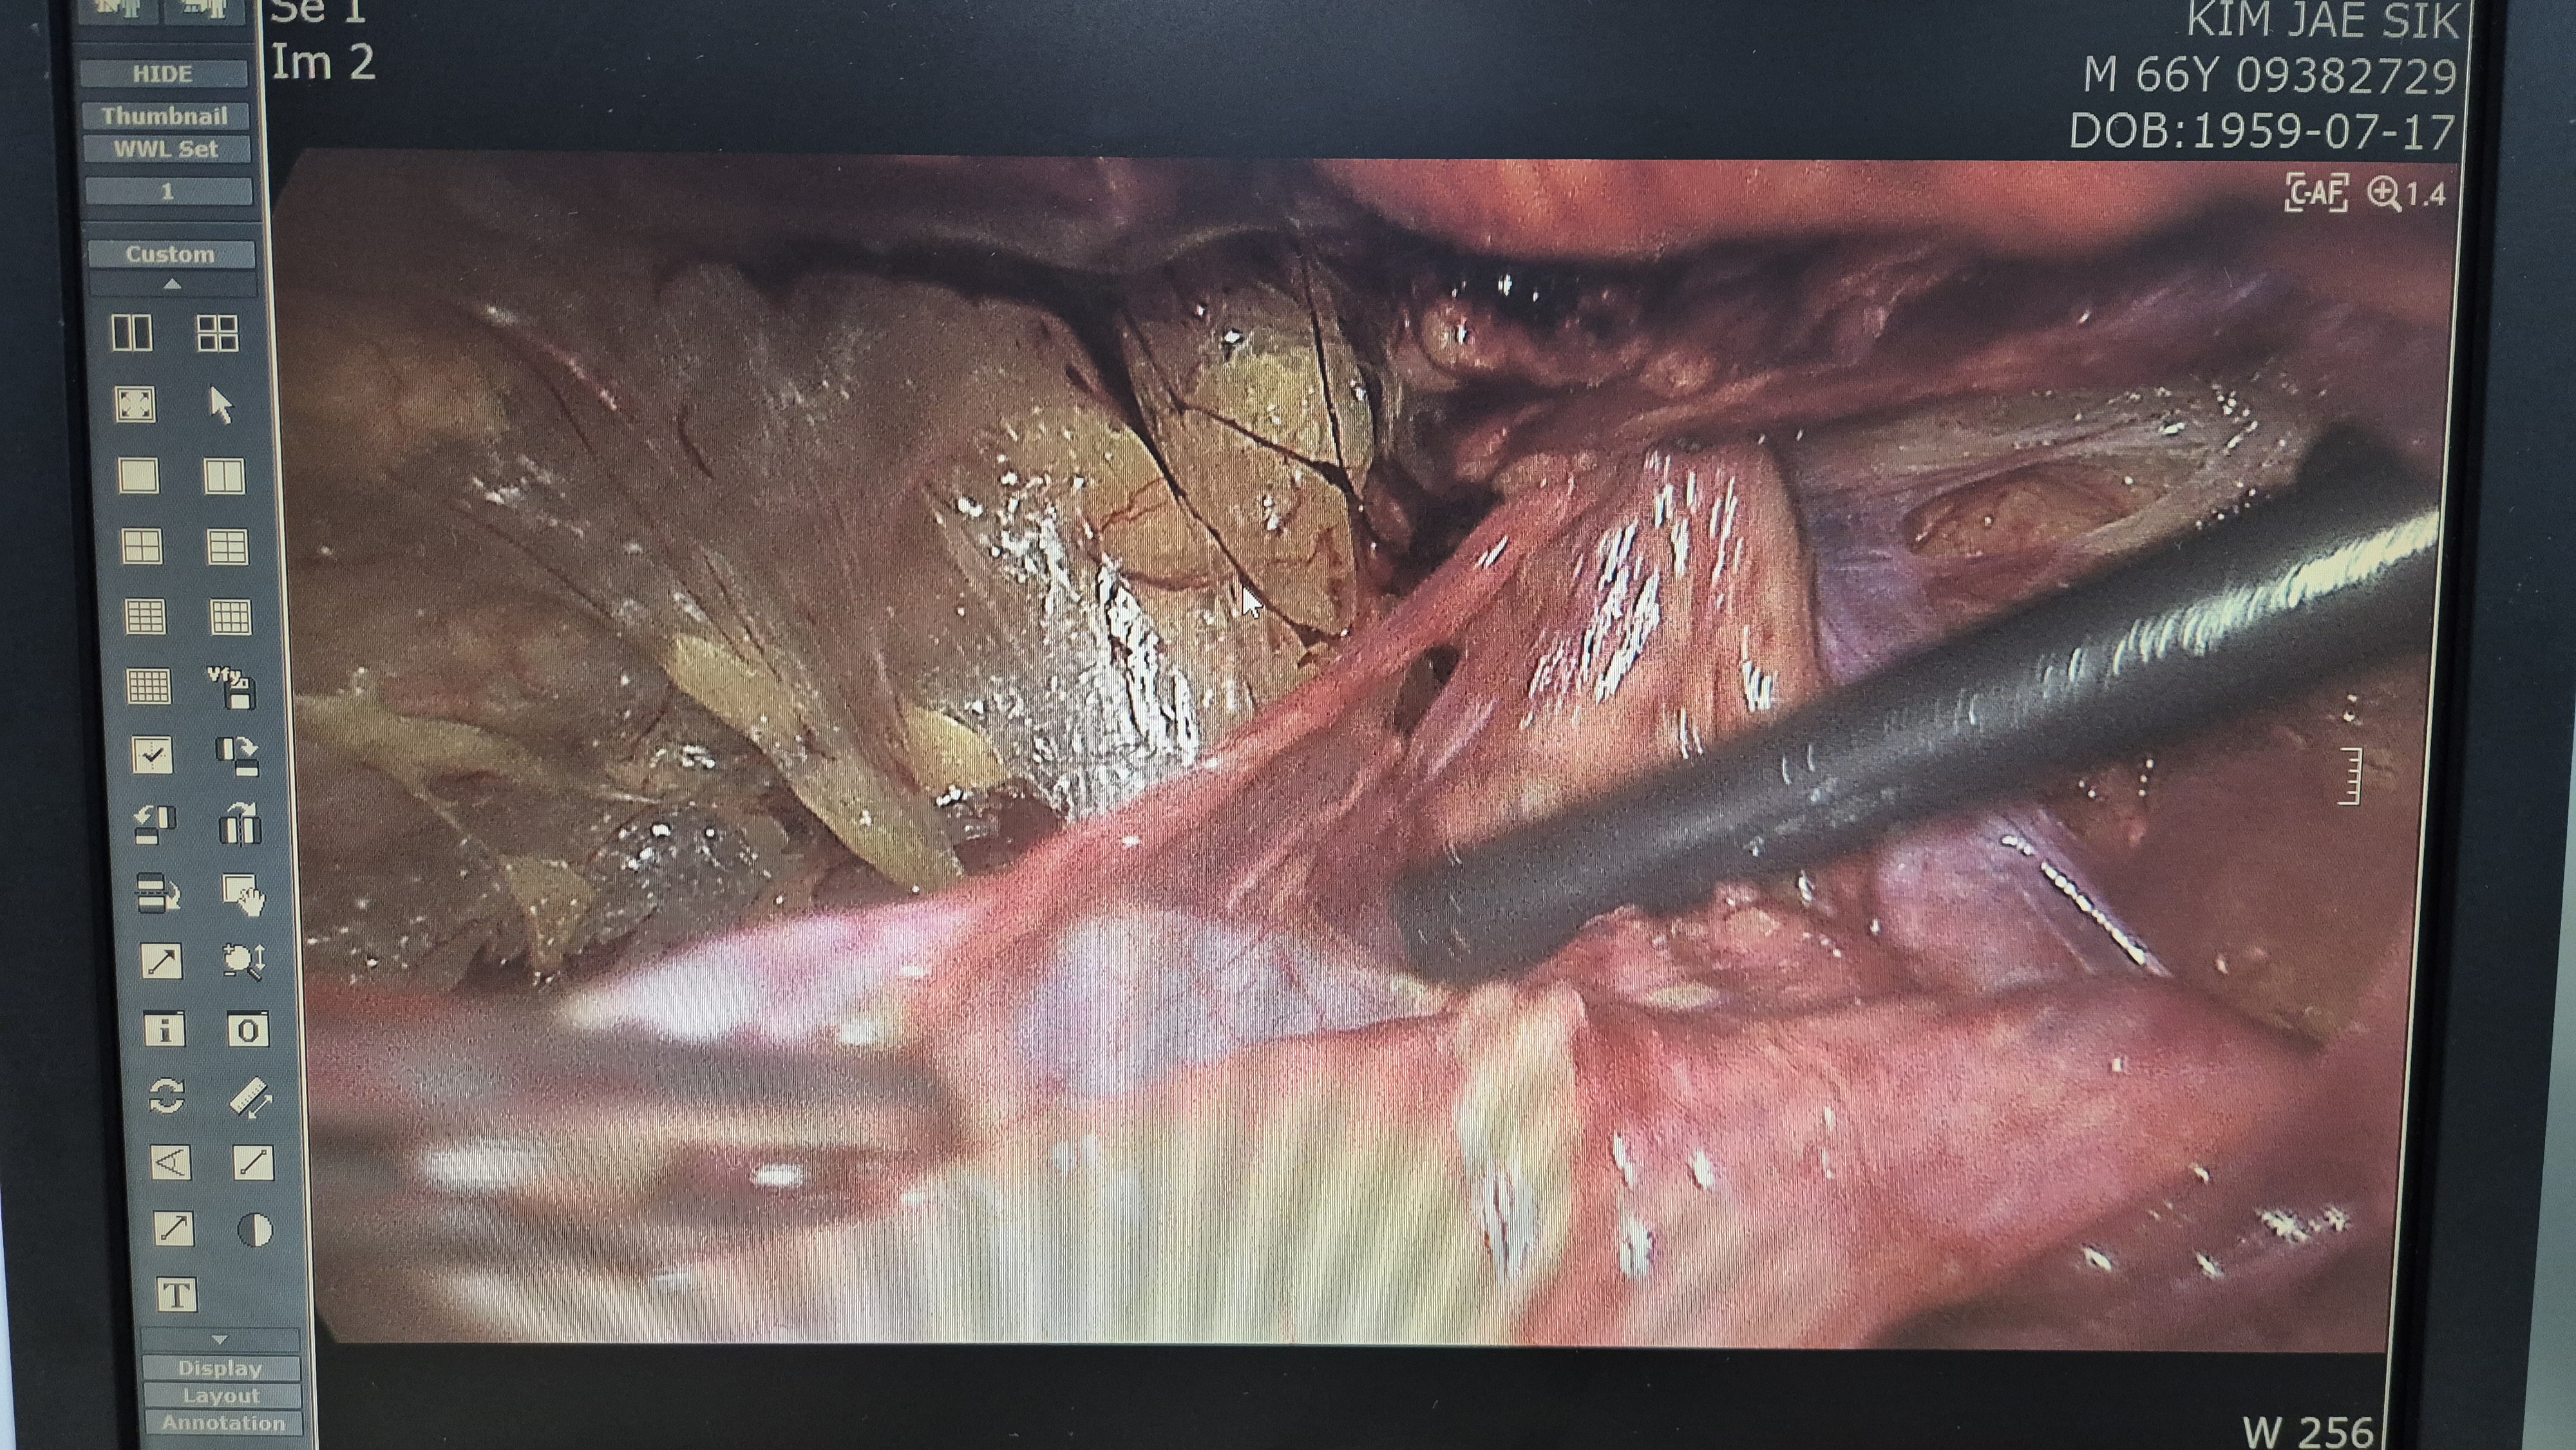

우측 서혜부 종물 주소로 내원하여 초음파 시행후 서혜부 탈장으로 확인되어,

방금 복강경 탈장교정술을 시행했습니다.

탈장 확인후.

박리.

메쉬로 고정.

수술은 15분 걸렸습니다.